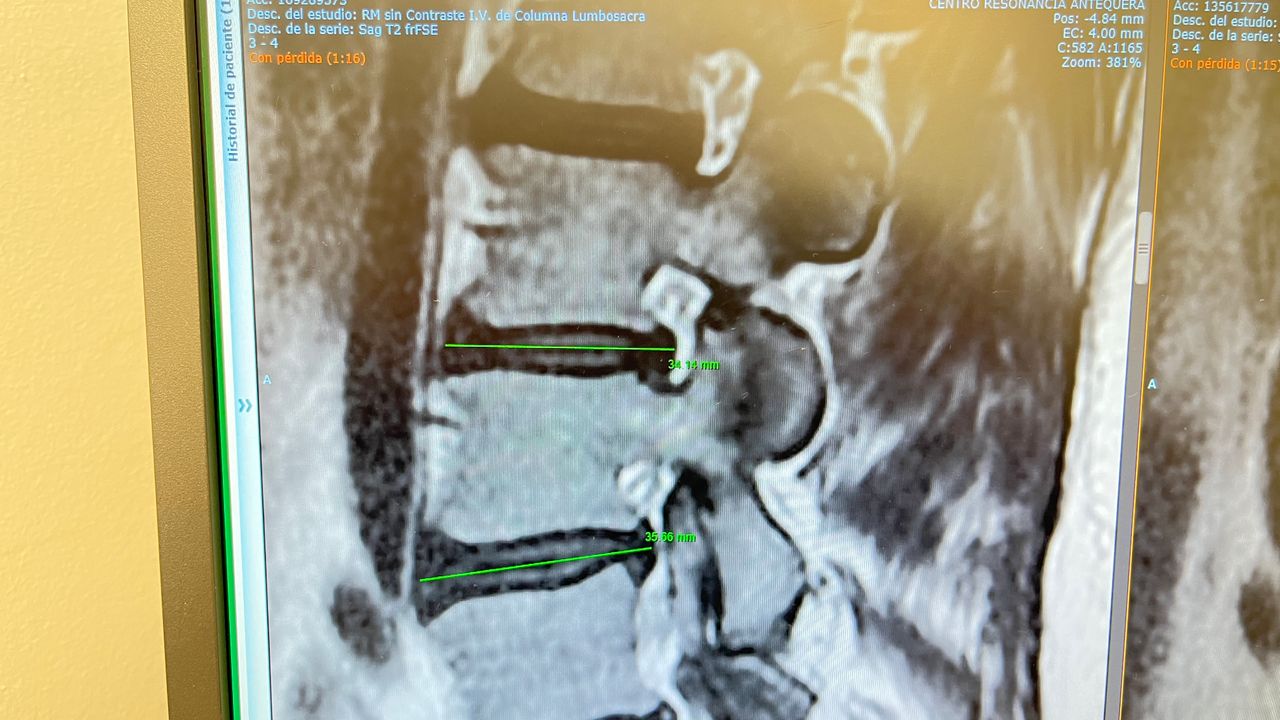

Galería